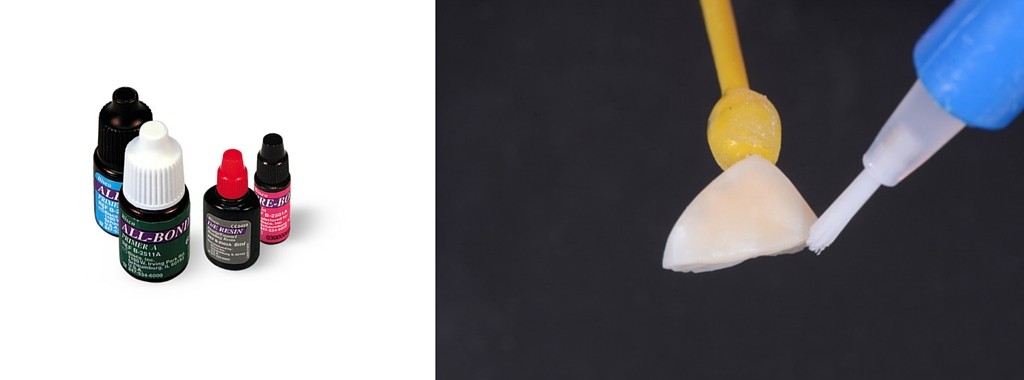

Application des primers et du bonding sur le morceau fracturé et photopolymérisation (All-Bond 2)

Application des primers et du bonding sur la dent et photopolymérisation (All-Bond 2)